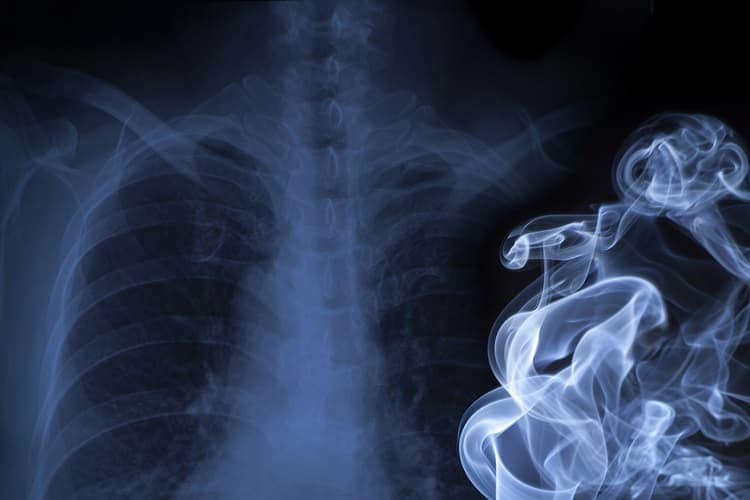

Cigarette smoking is the number one cause of lung cancer. Lung cancer also can be caused by using other types of tobacco (such as pipes or cigars), breathing secondhand smoke, being exposed to substances such as asbestos or radon at home or work, having certain gene mutations (unusual changes made when your body’s cells are dividing), or having a family history of lung cancer. Lung cancer can happen in people who never smoked or smoked fewer than 100 cigarettes in their lifetime.